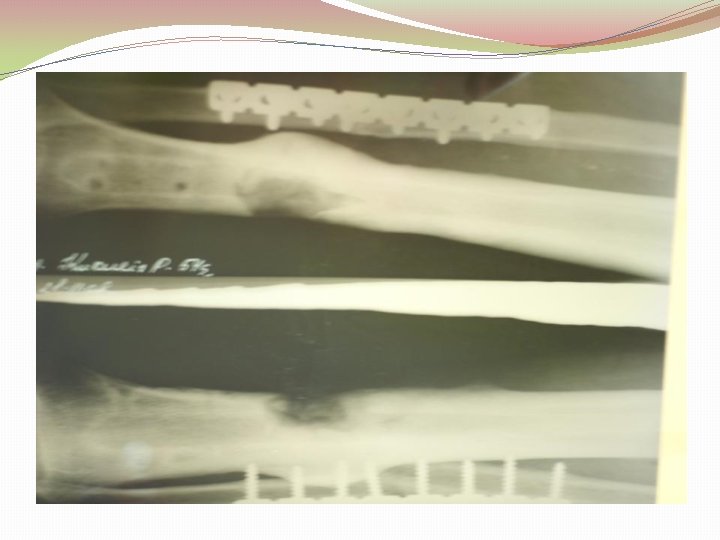

Biežums �Patzakis et al vaļēja tībijas gadījumā nelietojot antibiotiķus osteomielīta attīstība ir 24%, lietojot tikai 4, 5% � 2 -7% Stobra kaulu lūzumu gadījumos attīstās osteomielīts Lucian Fodor, Zvi Horesh, Alexander Lerner, Ytzhack Ramon, Isaac J. Peled, Yehuda Ullmann, The Distally Based Sural Musculoneurocutaneous Flap for Treatment of Distal Tibial Osteomyelitis, Plasic and Reconstuctive Surery 119: 2127, 2007.

Etioloģija Gustilo-Anderson vaļēju lūzumu klasifikācija I pakāpe brūce mazāka kā 1 cm (punktveida brūce) II pakāpe vaļēja brūce 1 -10 cm III pakāpe IIIA brūce vairāk kā 10 cm, nav mīksto audu defekta IIIB brūce vairāk, kā 10 cm ar mīksto audu bojājumu IIIC Plašs mīksto audu bojājums ar maģistrālo asinsvadu bojājums

Etioloģija Infekciju un amputāciju biežums pēc Gustilo-Anderson klasifikācijas Gustilo pakāpe Infekcijas biežums Amputācijas biežums I 0 -2% - II 2 -7% - IIIA 7% 2, 5% IIIB 10 -50% 5, 6% IIIC 25 -50% Gustilo RB; Merkow RL; Templeman. The management of open fractures. Current Concepts review. J Bone Joint Surg [Am], 72: 299 -304, 1990 Feb